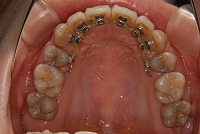

上は裏側、下は表側の矯正装置です。

患者様の美しさをそこねず、矯正治療ができたと思います。